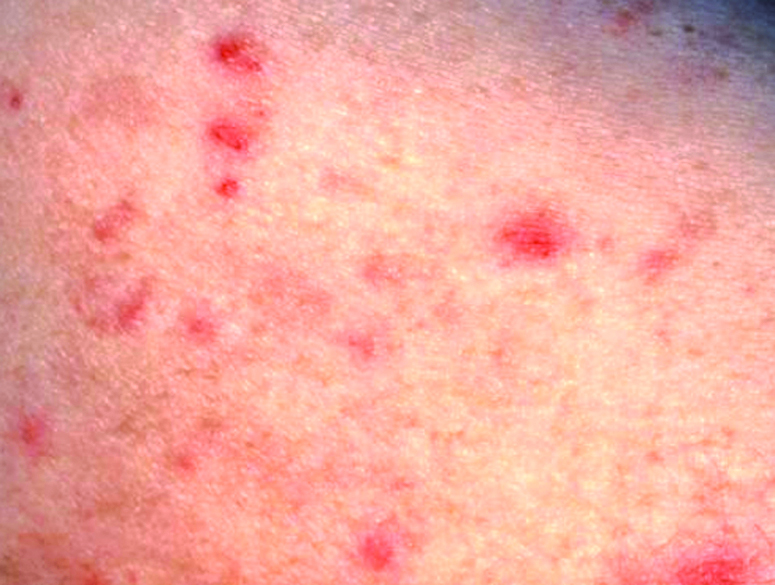

- Secondary syphilis:

- Papulosquamous thin papules on the trunk and extremities, palms and soles, fever and adenopathy

- Rash may resemble a drug eruption, pityriasis rosea and psoriasis